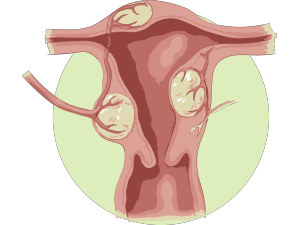

Твердий живіт при вагітності з'являється хоча б раз за весь період. Це означає, що матка знаходиться в тонусі. Якщо з'явилися перші симптоми, то обов'язково потрібно викликати лікаря і чекати його в лежачому положенні.

Сам по собі гіпертонус - це ризик викидня або пологів не за планом. Діагностику необхідно починати з опитування у лікаря. Він повинен уточнити, чи не хворів низ живота раніше, які є скарги і симптоми. У 60 відсотків усіх випадків саме больові відчуття в нижній області живота і є основними симптомами. Спостерігаються больові відчуття в крижах або попереку. Під час огляду застосовується метод пальпації. У розслабленому вигляді матка повинна бути м'якою. Гіпертонус діагностується, коли живіт стає напруженим і твердим. Пальпацію необхідно здійснювати, коли жінка лежить на спині. Ноги повинні бути зігнуті в колінах і в області таза. Так м'язи передньої черевної стінки не будуть мимоволі напружуватися. Це дасть можливість промацати і живіт, і органи в черевній області, і матку, і навіть визначити розташування плода всередині. Особливо важливо дослідити ділянку живіт для визначення передлежання малюка на останніх тижнях вагітності.

Чому живіт твердне? Причина може полягати в тому, що матка надмірно розтягується, що відбувається при вагітності з декількома плодами, многоводием або 1 плодом, але дуже великим.